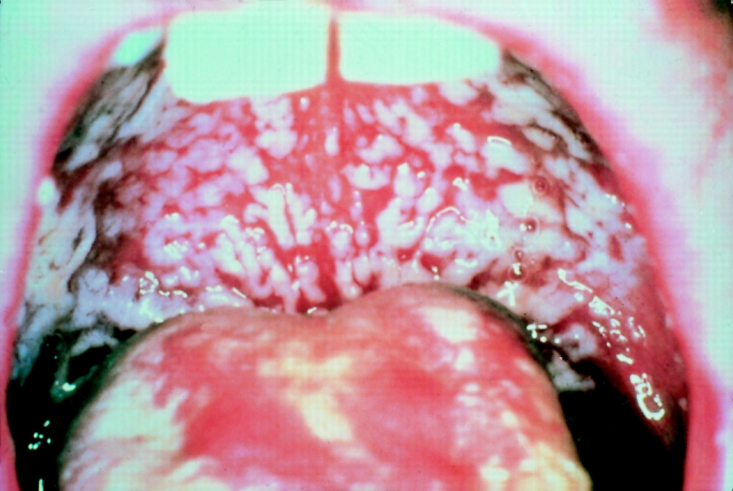

Thrush is a medical condition in which a fungus called Candida albicans overgrows in the mouth and throat.